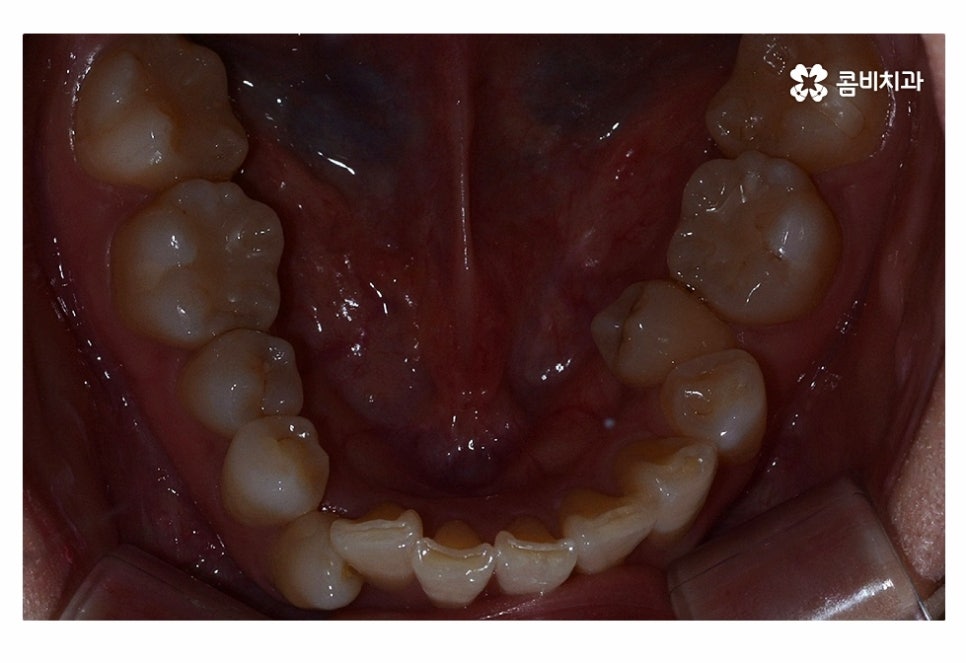

사진으로 보시는 환자분의 경우 윗니에 비해

아랫니가 좀 더 불규칙하다는 것을 알 수 있는데요.

오늘 사례의 환자분은 아랫니의 치열이 불규칙하고

교합을 고려할 때 전체교정을 진행해야 했지만

윗니가 약간 벌어진 경우나 불규칙한 정도가 심하지 않은 경우에는

부분설측교정으로 치료가 진행되는 경우도 있어요.